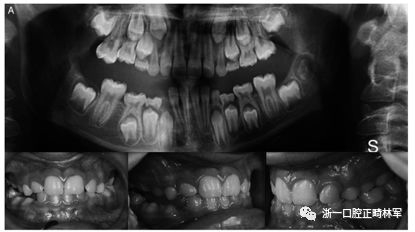

正畸文獻(xiàn)閱讀--原發(fā)性萌出失?。夯旌涎懒械呐R床和遺傳學(xué)研究

正畸文獻(xiàn)閱讀--原發(fā)性萌出失敗:混合牙列的臨床和遺傳學(xué)研究

圖1.(A,B)兩兄弟的口內(nèi)照片。全景:外顯子5的下游變體(CTCF結(jié)合位點(diǎn))rs113566258 SNPc.313±32A>G; 在外顯子16中的變體(位置3:46903467)c.1593-95 Del C,p.531 / 532; 外顯子10中的同義變體(位置3:46899419)c.1152 G>A.

兄弟姐妹被診斷為I型PFE并顯示雙邊呈現(xiàn)。該變體(PTH1R基因的外顯子5的下游c.313×32 A.G)發(fā)生在與轉(zhuǎn)錄因子相互作用的調(diào)節(jié)區(qū)中。除了這種突變之外,這些兄弟還受到第二個(gè)突變的影響,這些突變對(duì)每一個(gè)都是獨(dú)特的:一個(gè)兄弟姐妹(II:1)也存在在外顯子16的基因氨基末端發(fā)生的移碼缺失,c.1593DelC ,第(Pro532Leufs *)(圖1A,B)。在另一個(gè)同胞(II:3)中,鑒定出在蛋白質(zhì)氨基酸序列水平不引起變異的外顯子,c.1152GA(rs200475872;圖1A,B)中的同義變體,但涉及改變含氮堿。基于計(jì)算機(jī)分析,這種改變可能會(huì)影響mRNA的折疊并影響其半衰期和蛋白質(zhì)生產(chǎn)。在這個(gè)患者樣本中,在一個(gè)孤立的病例中發(fā)現(xiàn)了同樣的同義變體c.1152G.A,由于PFE而具有嚴(yán)重的開合(圖2)。

本研究中確定的低咬合的臨床特征與PFE基于基因診斷和萌出障礙診斷標(biāo)準(zhǔn)的應(yīng)用相一致。對(duì)特定相關(guān)牙科特征的仔細(xì)臨床檢查包括以下內(nèi)容:至少一顆牙包括低咬合,局限于后部區(qū)域,單側(cè)(38%;圖1A)和雙側(cè)呈現(xiàn)(35%;圖1B和2),至少有一個(gè)暫時(shí)性后牙(48%暫時(shí);圖1A,B和3A; 55%永久性,圖3B)。此外,觀察到牙面特征如下:由于受影響側(cè)的側(cè)向開放咬傷的嚴(yán)重程度而引起的垂直骨骼不對(duì)稱(35%;圖1A,B和圖3A,B);由下頜骨側(cè)向偏離組成的面部不對(duì)稱(圖1A,B和圖2;表4)。這種不對(duì)稱在單側(cè)開合患者中更為明顯。進(jìn)一步發(fā)現(xiàn)受影響的患者與先前報(bào)道的患者存在上頜骨收縮和III類牙齒/骨骼關(guān)系(28%;圖1A,B和圖2)。至少有一例患者出現(xiàn)了相對(duì)于9名患者的低咬合。表4總結(jié)了PTH1R的表型結(jié)果和相關(guān)的突變分析(N = 8)。